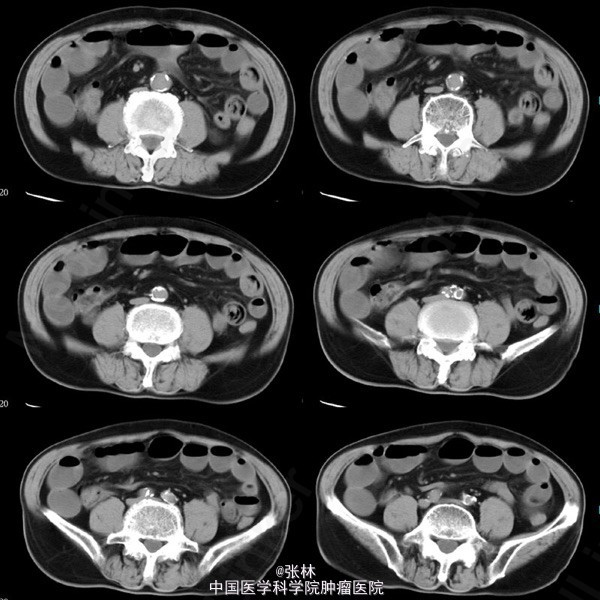

男性,72岁。 主诉:突发腹痛、腹胀伴呕吐1天。 现病史:患者1天前无诱因感全腹部疼痛,呈阵发性绞痛,无放射痛,疼痛开始不剧,伴有畏寒,呕吐胃内容物1次,量约30ml。遂到我院门诊就诊,考虑为急性胃肠炎,予抗炎、解痉护胃等支持治疗,症状未见好转,并进行性加重而入住我科。 专科检查:全腹稍胀,未见肠型及蠕动波,无上腹搏动。腹软,中下轻压痛,无反跳痛。全腹未及肿块,肠鸣音活跃,7次/分。 术中所见:探查见异物位于回肠距回盲部约50cm,大小约8*3*2cm,堵塞肠管,近端肠管充血水肿明显,肠管扩张最大处直径约8cm,未见浆膜层破裂损伤等,系膜无扭转,有少许渗液,探查全部小肠未及肿物腹腔内可见中等量黄色积液,稍浑浊,网膜及腹膜有少量脓苔。洗净腹腔内积液,于肿物边缘对肠系膜缘纵行切开约2cm,取出异物,为半个大小约8*3*2cm的冬菇。